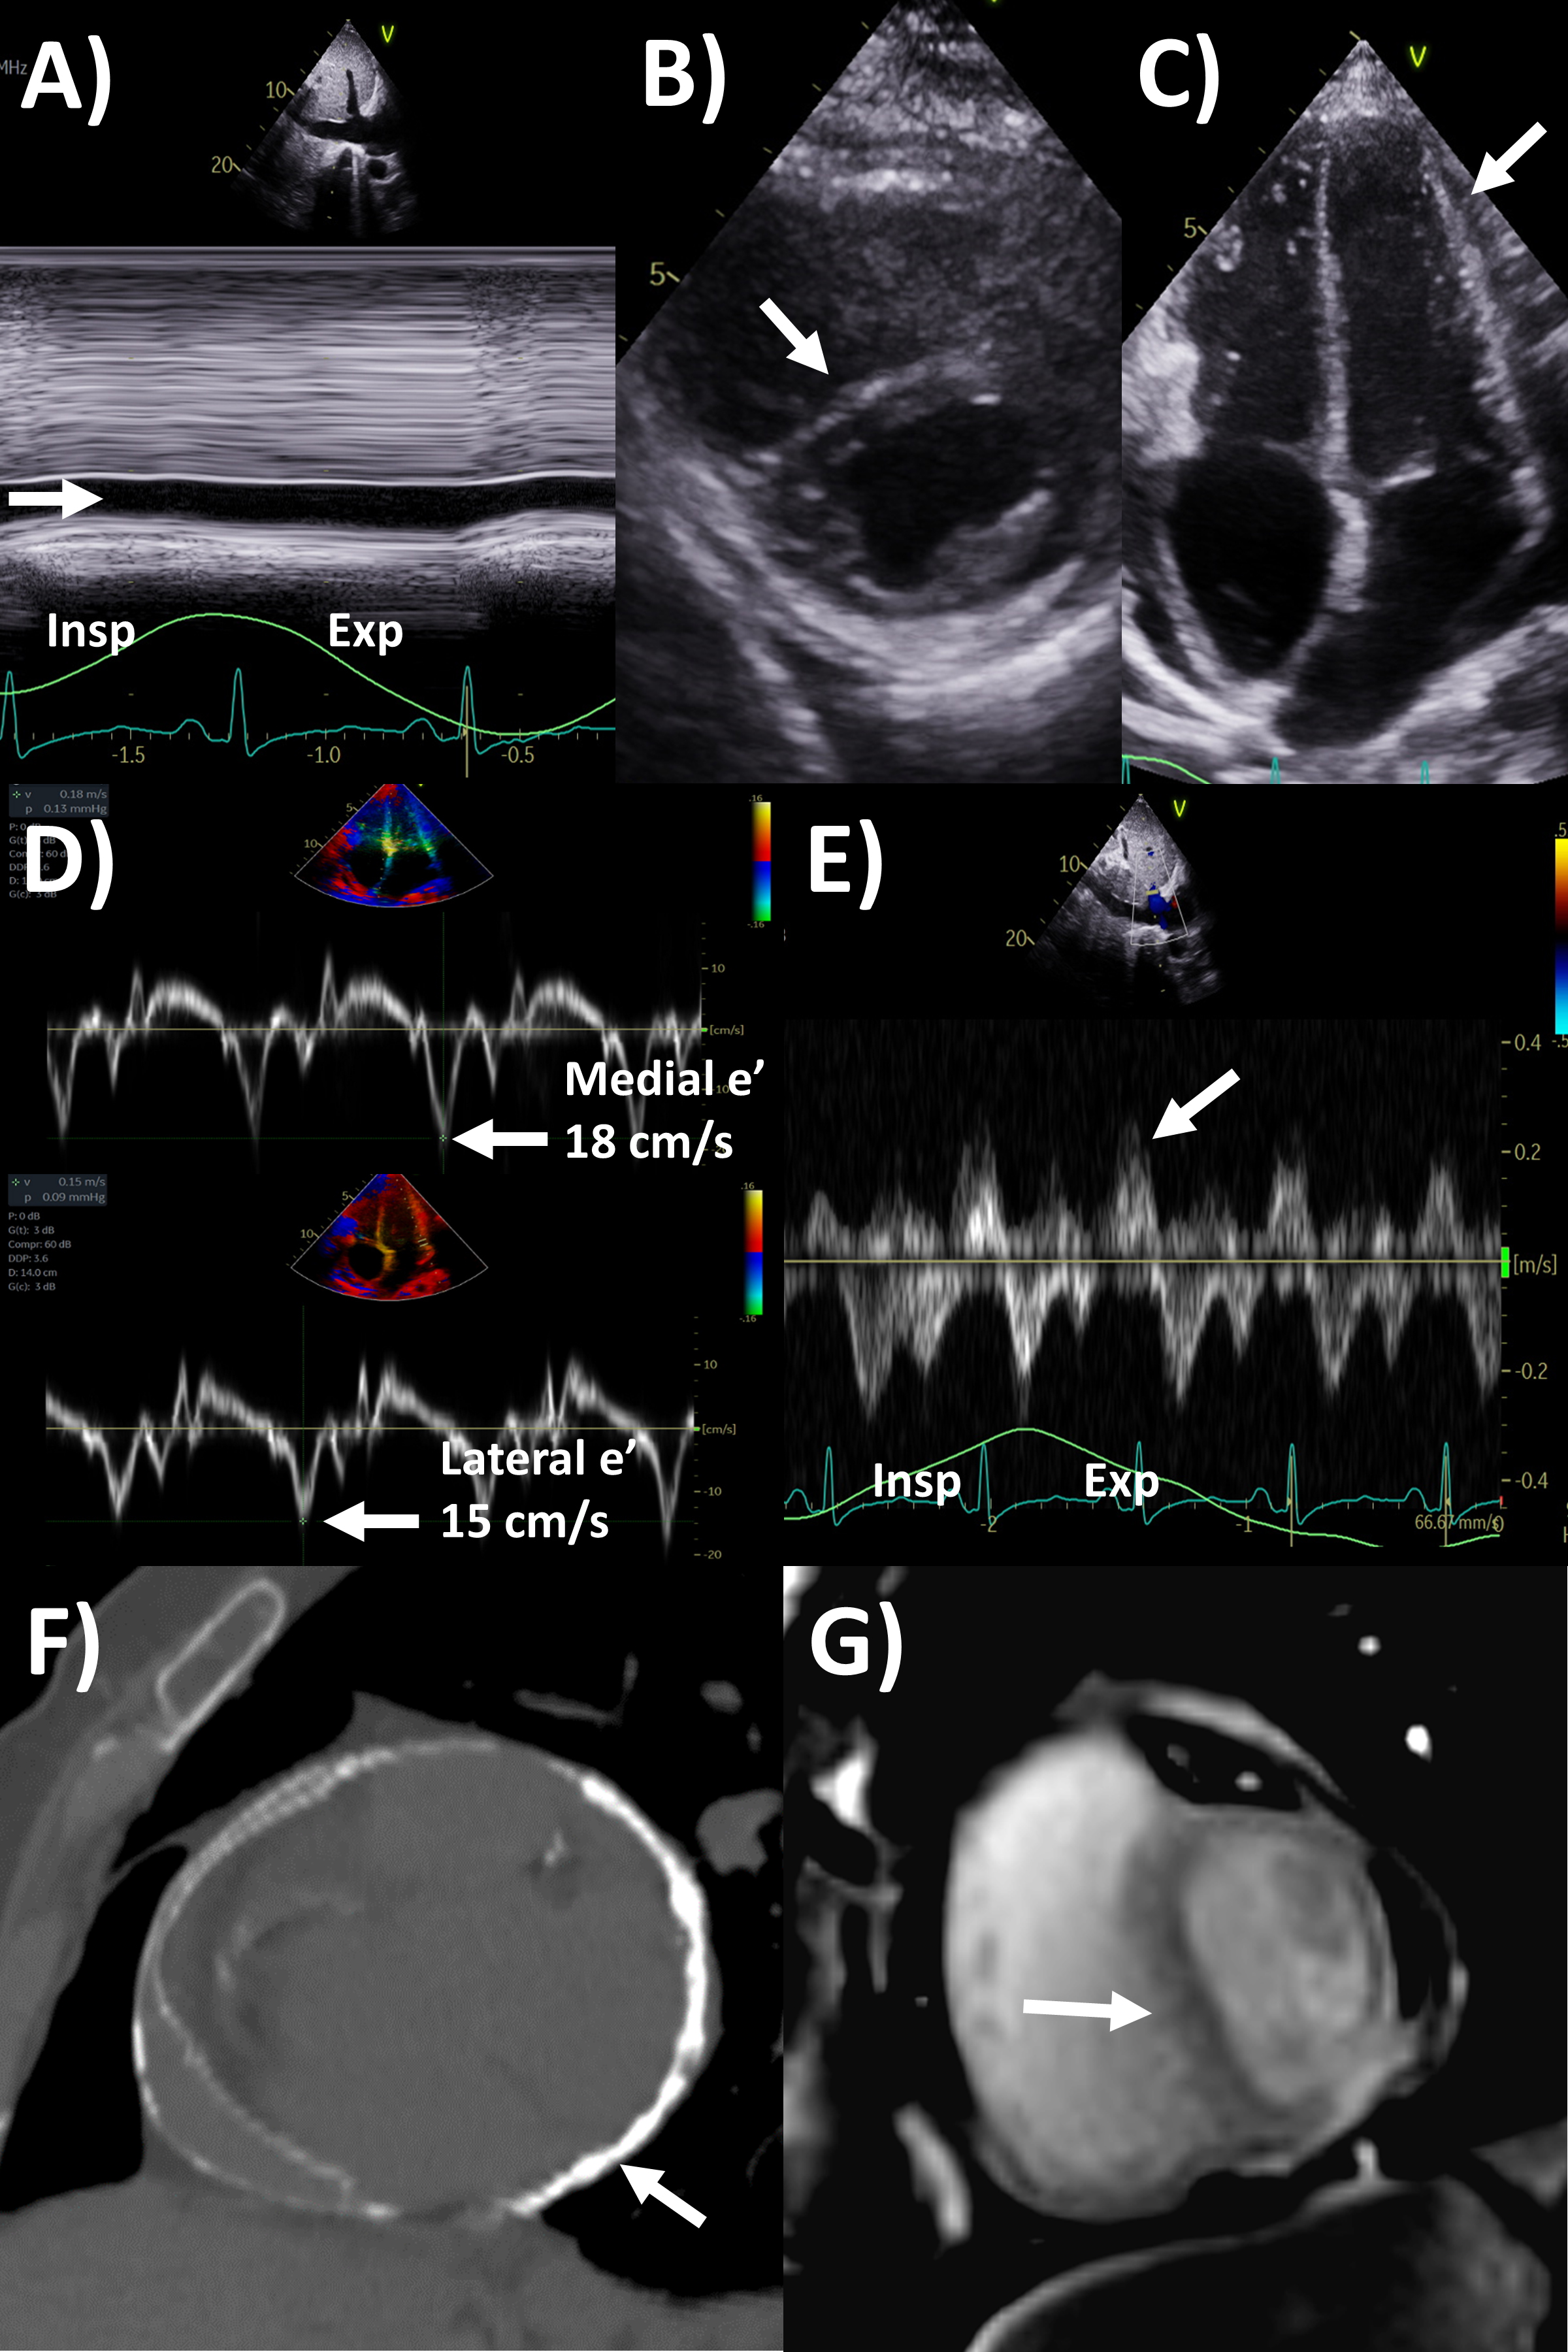

Pericarditis is classified based on duration of the acute episode—acute for those with pericarditis for less than 4 weeks; incessant for ongoing pericarditis between at least 4–6 weeks but less than 3 months without remission, chronic for pericarditis lasting for over 3 months, and recurrent pericarditis refers to 2 or more episodes of acute pericarditis with at least a 4–6 week interval without symptoms [1]. Recurrent pericarditis events occur in 15–30% after the first episode of pericarditis, and in 50% after 2 or more episodes [7, 8, 9, 10]. The diagnostic criteria for pericarditis based on guidelines include at least 2 out of the 4 criteria of (1) pericarditis chest pain, (2) pericardial rub on physical examination, (3) new ECG changes (widespread ST-elevation or PR depression) and new or worsening pericardial effusion; while other supporting features include elevated inflammatory markers (such as C-reactive protein, sedimentation rate and white cell count), and imaging evidence of pericardial inflammation (especially by MRI, Fig. 1) [1]. The main etiology categories of pericarditis are idiopathic, infective (most commonly viral, but also bacterial including tuberculosis, fungal and parasitic), autoimmune, iatrogenic (such as post-cardiac surgery and interventions), neoplastic, metabolic and drug-related. Tuberculosis pericarditis is mainly prevalent in developing countries and rare in developed countries.

Fig. 1.Multi-modality imaging features of acute pericarditis case. (A) Small pericardial effusion (arrow) subcostal view of echocardiography. (B) Pericardial thickening (arrow) on black-blood spin echo sequence of magnetic resonance imaging (MRI). (C) Severe circumferential increased pericardial signal indicating edema (arrow) on T2-weighted short tau inversion recovery imaging of MRI. (D) Severe circumferential pericardial enhancement indicating inflammation/fibrosis (arrow) on delayed gadolinium enhancement sequence of MRI.

Based on this criteria, echocardiography is the first-line imaging modality recommended for all patients undergoing pericarditis evaluation, although it is often normal [1, 2]. Apart from its main role in identifying pericardial effusion, echocardiography can examine the presence of tamponade physiology present in approximately 3% of acute pericarditis, identify pericardial thickening, evaluate for the presence of regional wall motion abnormalities that may indicate concurrent myocardial involvement (myo-pericarditis) in approximately 5%, or look for alternative diagnoses like acute coronary syndrome or aortic dissection [2]. Echocardiography is also important during follow-up after initial pericarditis event for resolution of pericardial effusion if it had been present, along with signs of constrictive physiology, discussed in the later section.

Perhaps the most important application of MRI in pericardial diseases is its ability to identify pericardial inflammation [2, 10]. The key features include pericardial thickening, best assessed on black-blood spin echo sequences; pericardial edema, assessed using T2-short tau inversion recovery (STIR) sequences as high signal intensity; and inflammation or fibrosis on late gadolinium enhancement sequences again as high signal intensity (Fig. 1) [2, 13, 14]. Histologically, pericardial late gadolinium enhancement correlates with fibroblastic proliferation, neovascularization and chronic inflammation and granulation tissue [15]. Some studies have reported moderate sensitivity (63–68%) and high specificity (up to 100%) of the T2-STIR sequence for acute pericarditis, however this is significantly lower in practice, as elevated signal can also be seen with pericardial effusion or MRI artefact [16, 17]. The delayed enhancement sequence has been reported to have moderate to high 65–100% sensitivity and high specificity 99–100% for pericarditis, however again in practice this is lower with pericardial fat, pleuritis and artefact potentially interfering with scan interpretation, and fat saturated pulses added to delayed enhancement sequences are recommended to improve the positive predictive value of pericardial enhancement [14, 16, 17, 18]. MRI can also evaluate for concomitant myocardial involvement and inflammation (myocarditis) where they be left ventricular dysfunction and regional wall motion abnormalities on cine sequences; increased myocardial signal intensity on T2-STIR or elevated T2-mapping values implying myocardial edema; increased myocardial signal intensity on delayed gadolinium enhancement sequences or elevated T1-mapping values consistent with myocardial inflammation and fibrosis; and along with early gadolinium enhancement suggesting hyperemia [19]. As such MRI is strongly recommended in the initial diagnosis of pericarditis with a complimentary role to clinical, inflammatory biomarkers and echocardiography assessment, especially if the diagnosis remains uncertain after the other tests [1, 2, 10].